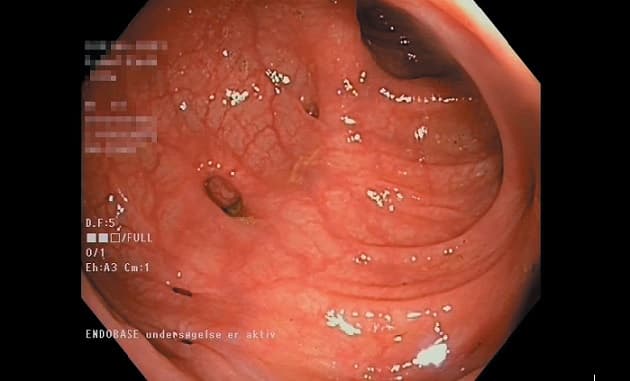

©. Divertikulose ved endoskopi.

Over 60% af ældre over 80 år har colondivertikulose, og livstidsrisikoen for at udvikle en komplicerende akut divertikulitis hos disse personer antages at være 10-25%. Mange guidelines anbefaler koloskopi i en rolig fase efter CT-verificeret divertikulitis. I deres statusartikel konkluderer Erritzøe et al, at risikoen for at have en ikkeerkendt kolorektal cancer især er øget hos patienter med kompliceret divertikulitis, mens der ikke er evidensbaseret gevinst ved at foretage en kontrolendoskopi efter en ukompliceret divertikulitis.